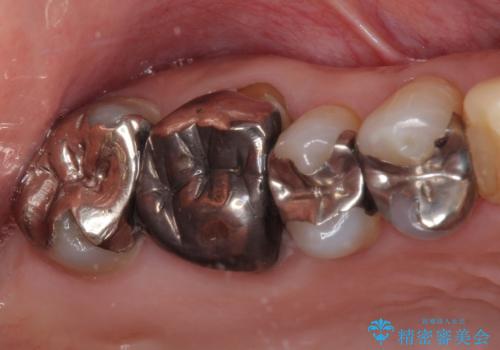

- 右上の小臼歯部に咬んだときに強い痛みを感じるとのことで来院された患者様です。

診査を行った結果、根管治療を行った後にオールセラミッククラウンにて補綴する治療計画となりました。

咬んだときの痛みに加えて夜間のズキズキする痛みもありましたが、1回目の根管治療実施後間もなく咬んだときの痛みがなくなったので、2回目に根管充填を行いました。